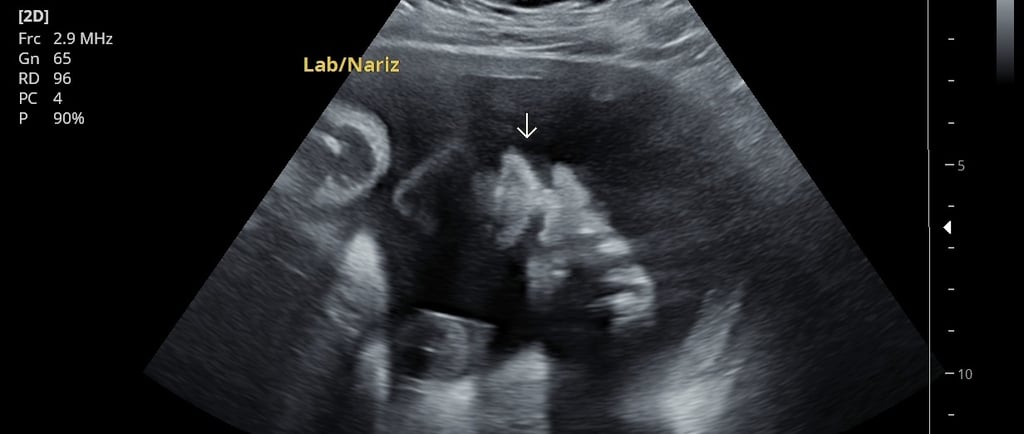

Ultrasonido 2D: el estudio esencial para el control del embarazo

El ultrasonido 2D, en escala de grises, es el más utilizado a lo largo del embarazo. Sirve para:

Aunque su imagen no es tridimensional, es el estudio con mayor valor diagnóstico y el que se recomienda hacer en cada trimestre.